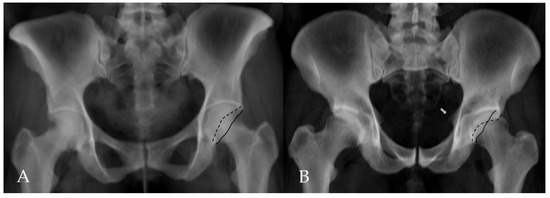

Figure 3.

Assessment of additional morphological parameters of femoroacetabular impingement on a CT-based virtual pelvic radiograph. (A) Negative acetabular crossover sign. The black solid line represents the posterior acetabular wall, and the black dashed line represents the anterior acetabular wall. (B) Positive acetabular crossover sign with an associated ischial spine sign (white arrow), suggestive of pincer-type femoroacetabular impingement and acetabular retroversion.